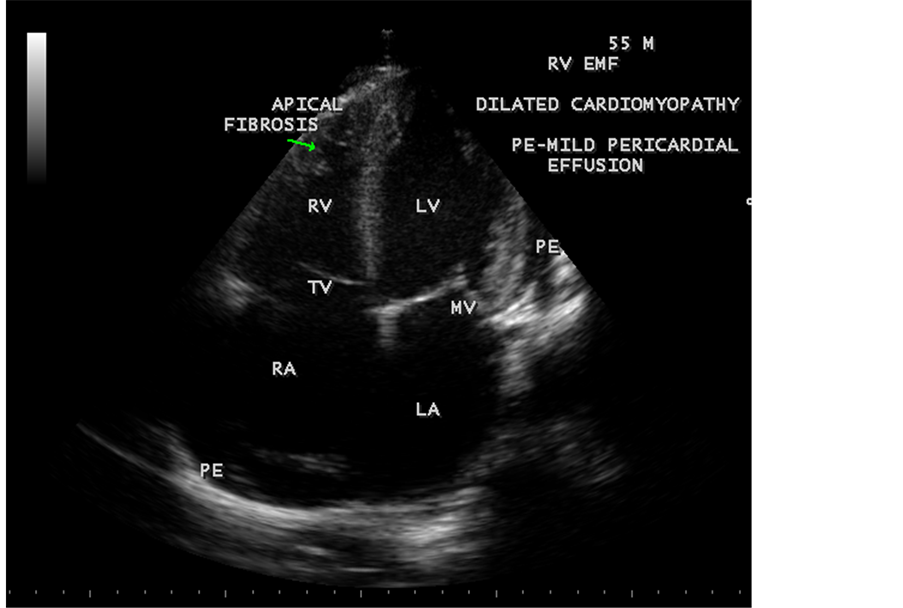

Figure 73. Showing the dilated cardiomyopathy in a 55-year-old male in EMF.

RV EMF was detected antenatally in a 22-year-old woman with 8 months amenorrhea as in Figure 67. Endomyocardial fibrosis with left ventricular endocardial calcification and subvalvular fibrosis was detected in a new born with complete AV (atrioventricular) septal defect as shown in Figure 68 to Figure 72. EMF associated with fibrosis of papillary muscle and aneurysmal left ventricle is shown in Figure 74 and Figure 75 in a 56-year-old female. RV EMF associated with right sided pleural effusion, massive ascites and smoke (spontaneous echo contrast) in both ventricles are shown in Figure 76 to Figure 82 in a 42-year-old male. Classical case of RV EMF was shown in Figure 83 and Figure 84 in a 55-year-old male.